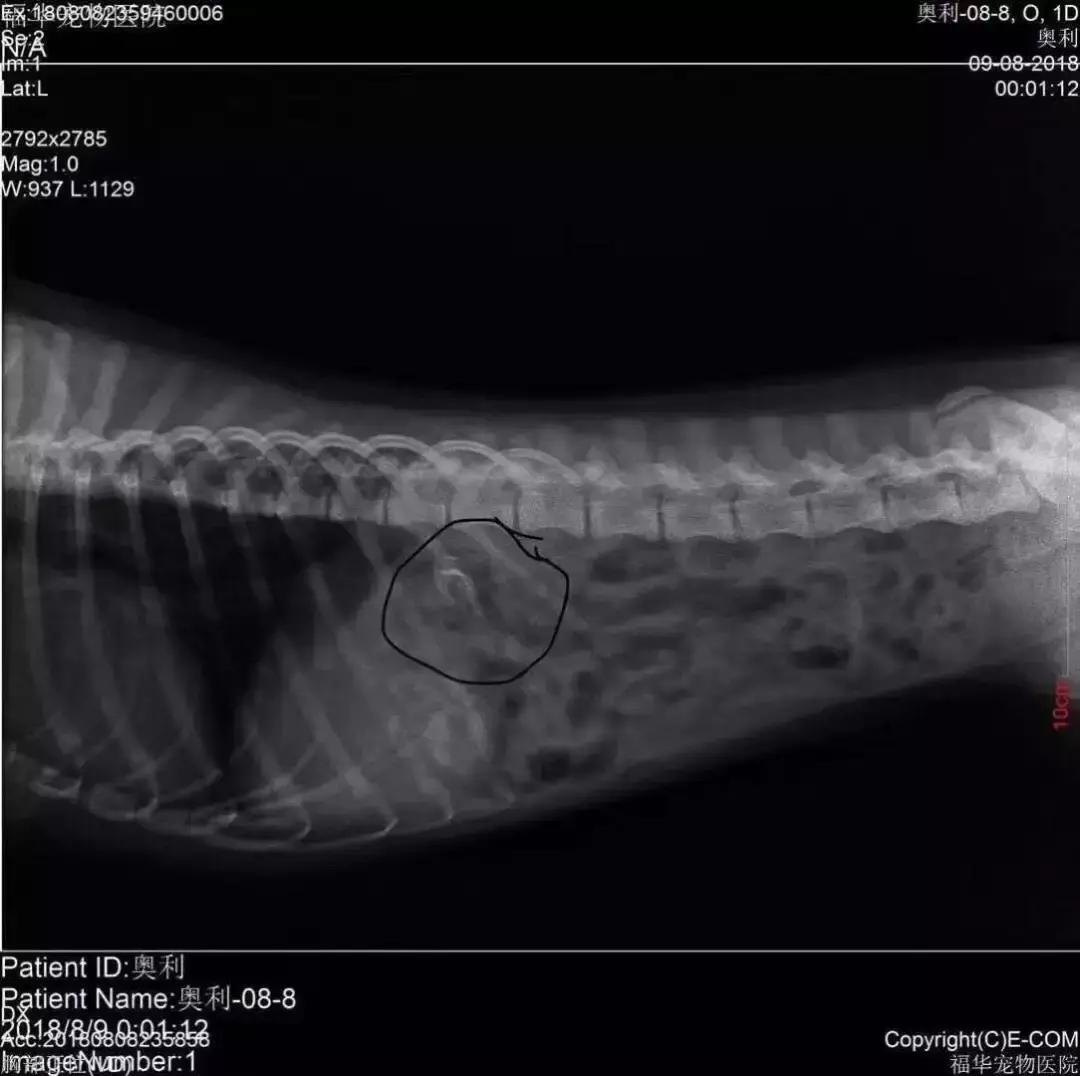

“该不会狗狗也吃了这些火腿肠吧?” 陈太太一想到这里,马上联系了女儿,连夜将小狗送到了宠物医院治疗。在给狗狗拍了片之后,医生果然发现一个鱼钩已经溜到了它的身体里。

经过医生连夜抢救和治疗,这个险些要命的鱼钩终于被取了出来。